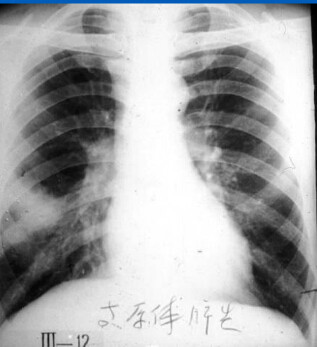

肺炎支原体肺炎:

肺部多种形态的浸润影,呈节段性分布,以肺下野为多见,也有从肺门附近向外伸展者。